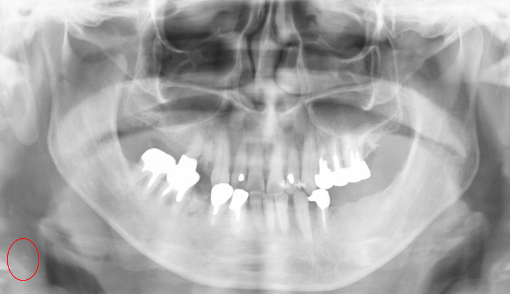

また,歯科パノラマX線に写る頸動脈の石灰化をAIで自動検出し,脳卒中などの重症化予防と医科受診の早期化に役立てる研究です. 歯科で撮影済み画像の二次活用により,日常診療での早期スクリーニングへの実装を目指します. 学習データが少なくても高精度を達成できることが特徴です.(関西大学・画像処理工学研究室と松本歯科大学との共同研究)